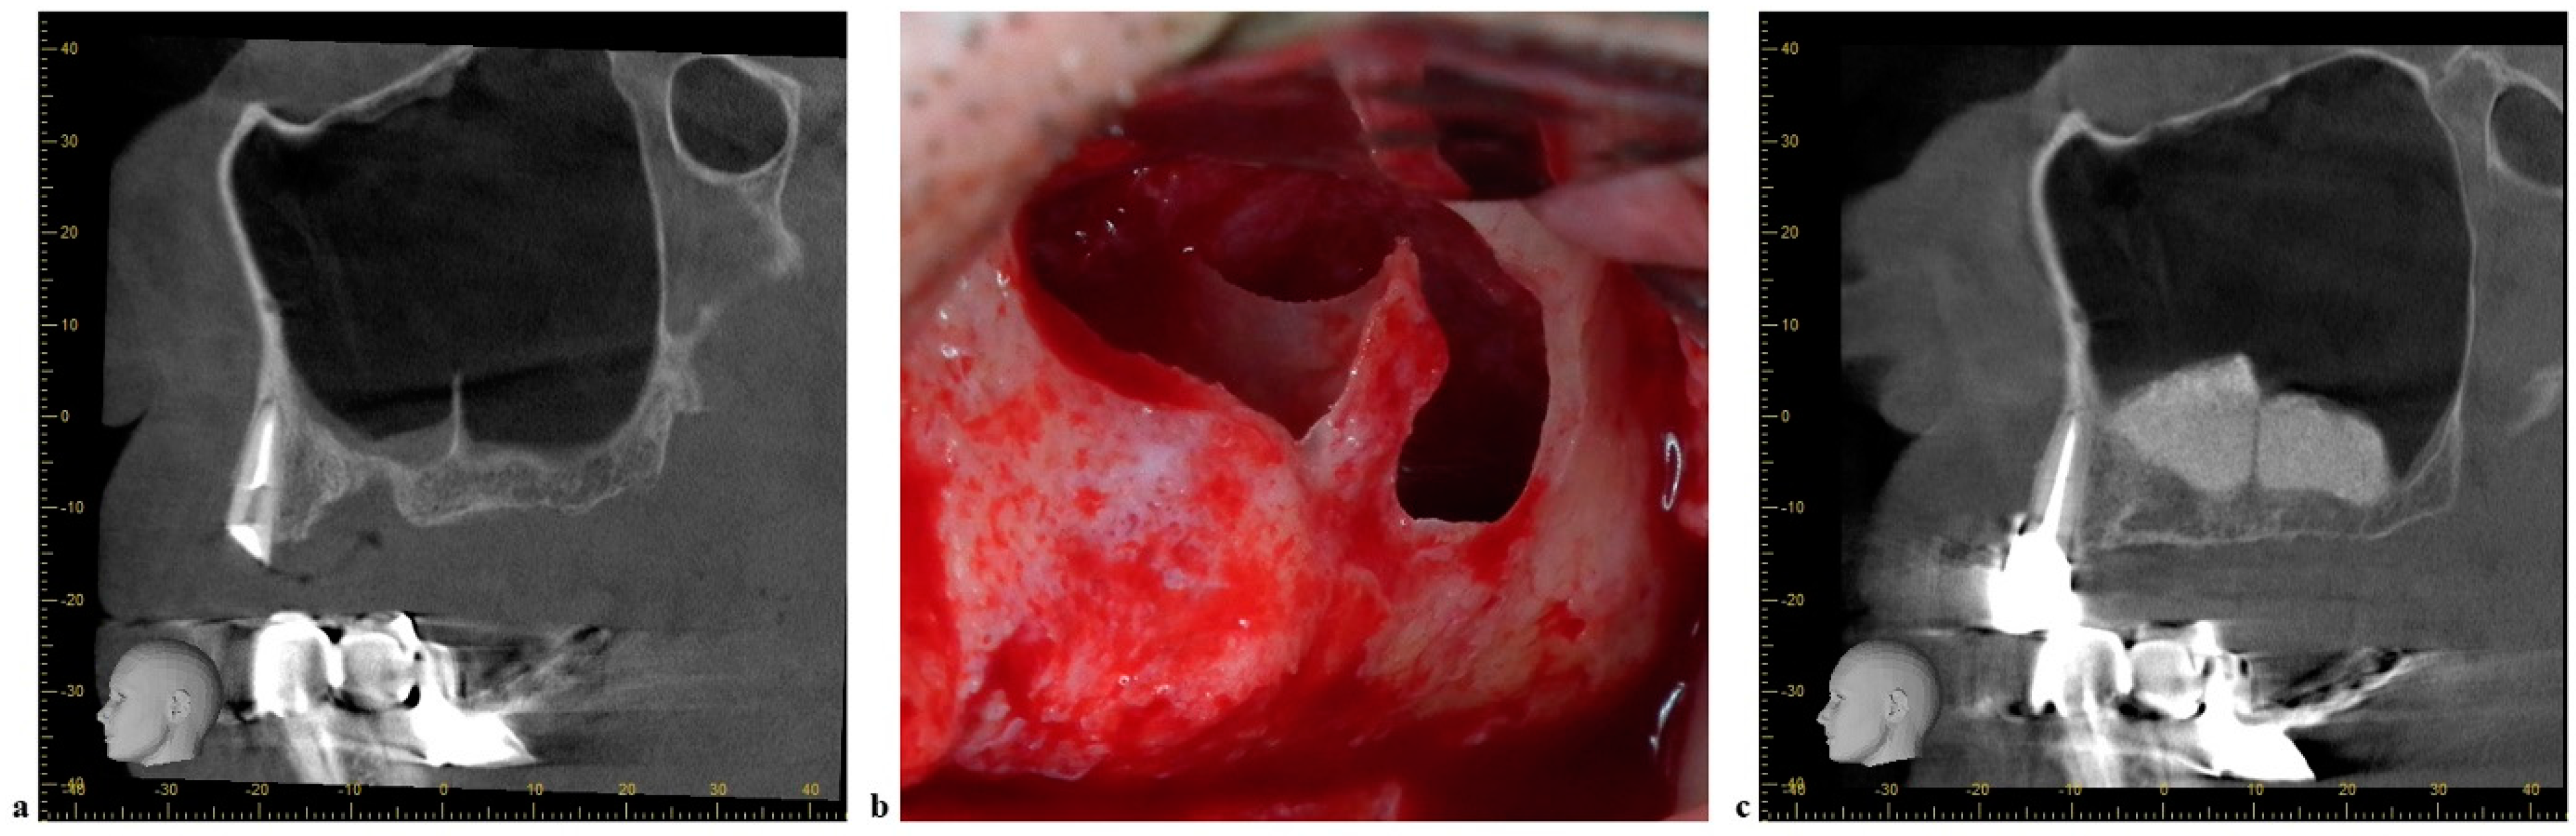

- Barbu, H.M.; Iancu, S.A.; Jarjour Mirea, I.; Mignogna, M.D.; Samet, N.; Calvo-Guirado, J.L. Management of Schneiderian Membrane Perforations during Sinus Augmentation Procedures: A Preliminary Comparison of Two Different Approaches. J. Clin. Med. 2019, 8, 1491. [Google Scholar] [CrossRef] [PubMed] [Green Version]

- Irinakis, T.; Dabuleanu, V.; Aldahlawi, S. Complications During Maxillary Sinus Augmentation Associated with Interfering Septa: A New Classification of Septa. Open Dent. J. 2017, 11, 140–150. [Google Scholar] [CrossRef] [PubMed] [Green Version]

- Okada, T.; Kawana, H. Two-Step Procedure for the Treatment of a Maxillary Sinus with Complex Sinus Septa: A Highly Predictive Method for Sinus Floor Augmentation After Perforation of the Maxillary Sinus Membrane. Int. J. Periodontics Restor. Dent. 2019, 39, e175–e180. [Google Scholar] [CrossRef]

- Jung, J.; Hwang, B.Y.; Kim, B.S.; Lee, J.W. Floating septum technique: Easy and safe method maxillary sinus septa in sinus lifting procedure. Maxillofac. Plast. Reconstr. Surg. 2019, 41, 54. [Google Scholar] [CrossRef] [PubMed]